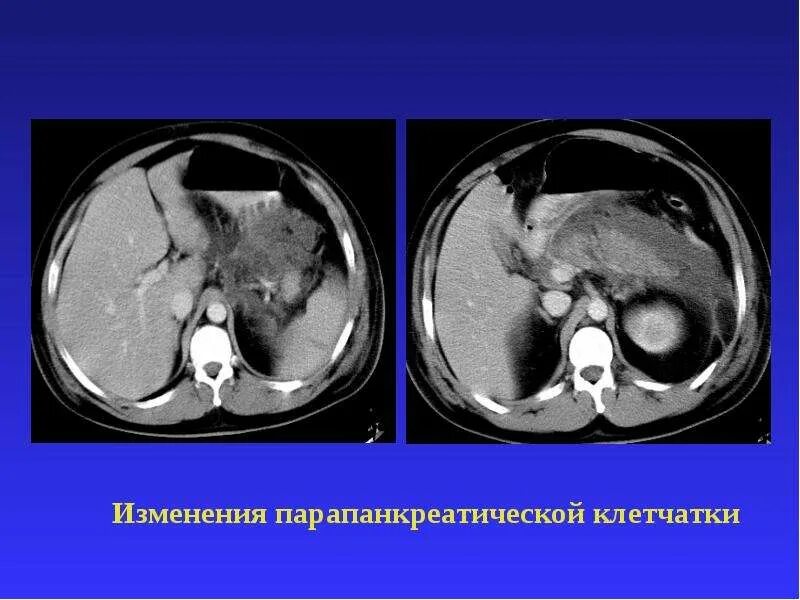

Инфильтрация паранефральной клетчатки на кт. параколитическая клетчатка кт. парапанкреатическая клетчатка инфильтрирована. перипанкреатический инфильтрат.Кт при остром панкреатите. парапанкреатическая клетчатка. кт диагностика панкреатита. острый отечный панкреатит кт.Парапанкреатическая клетчатка. поддиафрагмальное пространство. внебрюшинное поддиафрагмальное пространство. парапанкреатическая клетчатка инфильтрирована.Парапанкреатическая клетчатка что это значитКлетчатка анатомия. понятие о клетчатке в анатомии. основы клинической анатомии. клетчатка понятие.Парапанкреатическая клетчатка что это значитПарапанкреатическая клетчатка. парапанкреатическая клетчатка инфильтрирована. парапанкреатическая инфильтрация. парапанкреатическая клетчатка дифференцирована.Парапанкреатическая клетчатка что это значитПарапанкреатическая клетчатка что это значитХронический панкреатит на кт. парапанкреатическая клетчатка на кт. кт поджелудочной железы. поджелудочная железа на рентгенограмме.Парапанкреатическая клетчатка что это значитПарапанкреатическая клетчатка что это значитПарапанкреатический инфильтрат. парапанкреатическая клетчатка дифференцирована.Парапанкреатическая клетчатка что это значитПарапанкреатическая клетчатка что это значитПарапанкреатическая клетчатка поджелудочной железы. отек парапанкреатической клетчатки. парапанкреатическая инфильтрация. острый деструктивный панкреатит кт.Парапанкреатическая клетчатка что это значитПарапанкреатическая клетчатка что это значитПарапанкреатическая клетчатка что это значитПарапанкреатическая клетчатка что это значитПарапанкреатическая клетчатка что это значитПарапанкреатический инфильтрат. перипанкреатический инфильтрат. парапанкреатическая псевдокиста на кт.Парапанкреатическая клетчатка что это значитПарапанкреатическая клетчатка что это значитПарапанкреатическая клетчатка что это значитПарапанкреатическая клетчатка что это значитПарапанкреатическая клетчатка что это значитПарапанкреатическая клетчатка что это значитПарапанкреатическая клетчатка что это значитПарапанкреатическая клетчатка что это значитПарапанкреатическая клетчатка что это значитПарапанкреатическая клетчатка поджелудочной железы. перипанкреатический инфильтрат. осложнения острого панкреатита презентация. перипанкреатическая клетчатка.Парапанкреатическая клетчатка что это значитКисты и свищи поджелудочной железы. инфильтрация парапанкреатической клетчатки. истинные кисты поджелудочной железы классификация. парапанкреатическая клетчатка поджелудочной железы.Парапанкреатическая клетчатка что это значитПарапанкреатическая клетчатка что это значитПарапанкреатическая клетчатка что это значитПарапанкреатическая клетчатка что это значитПарапанкреатическая клетчатка что это значитПарапанкреатическая клетчатка что это значит